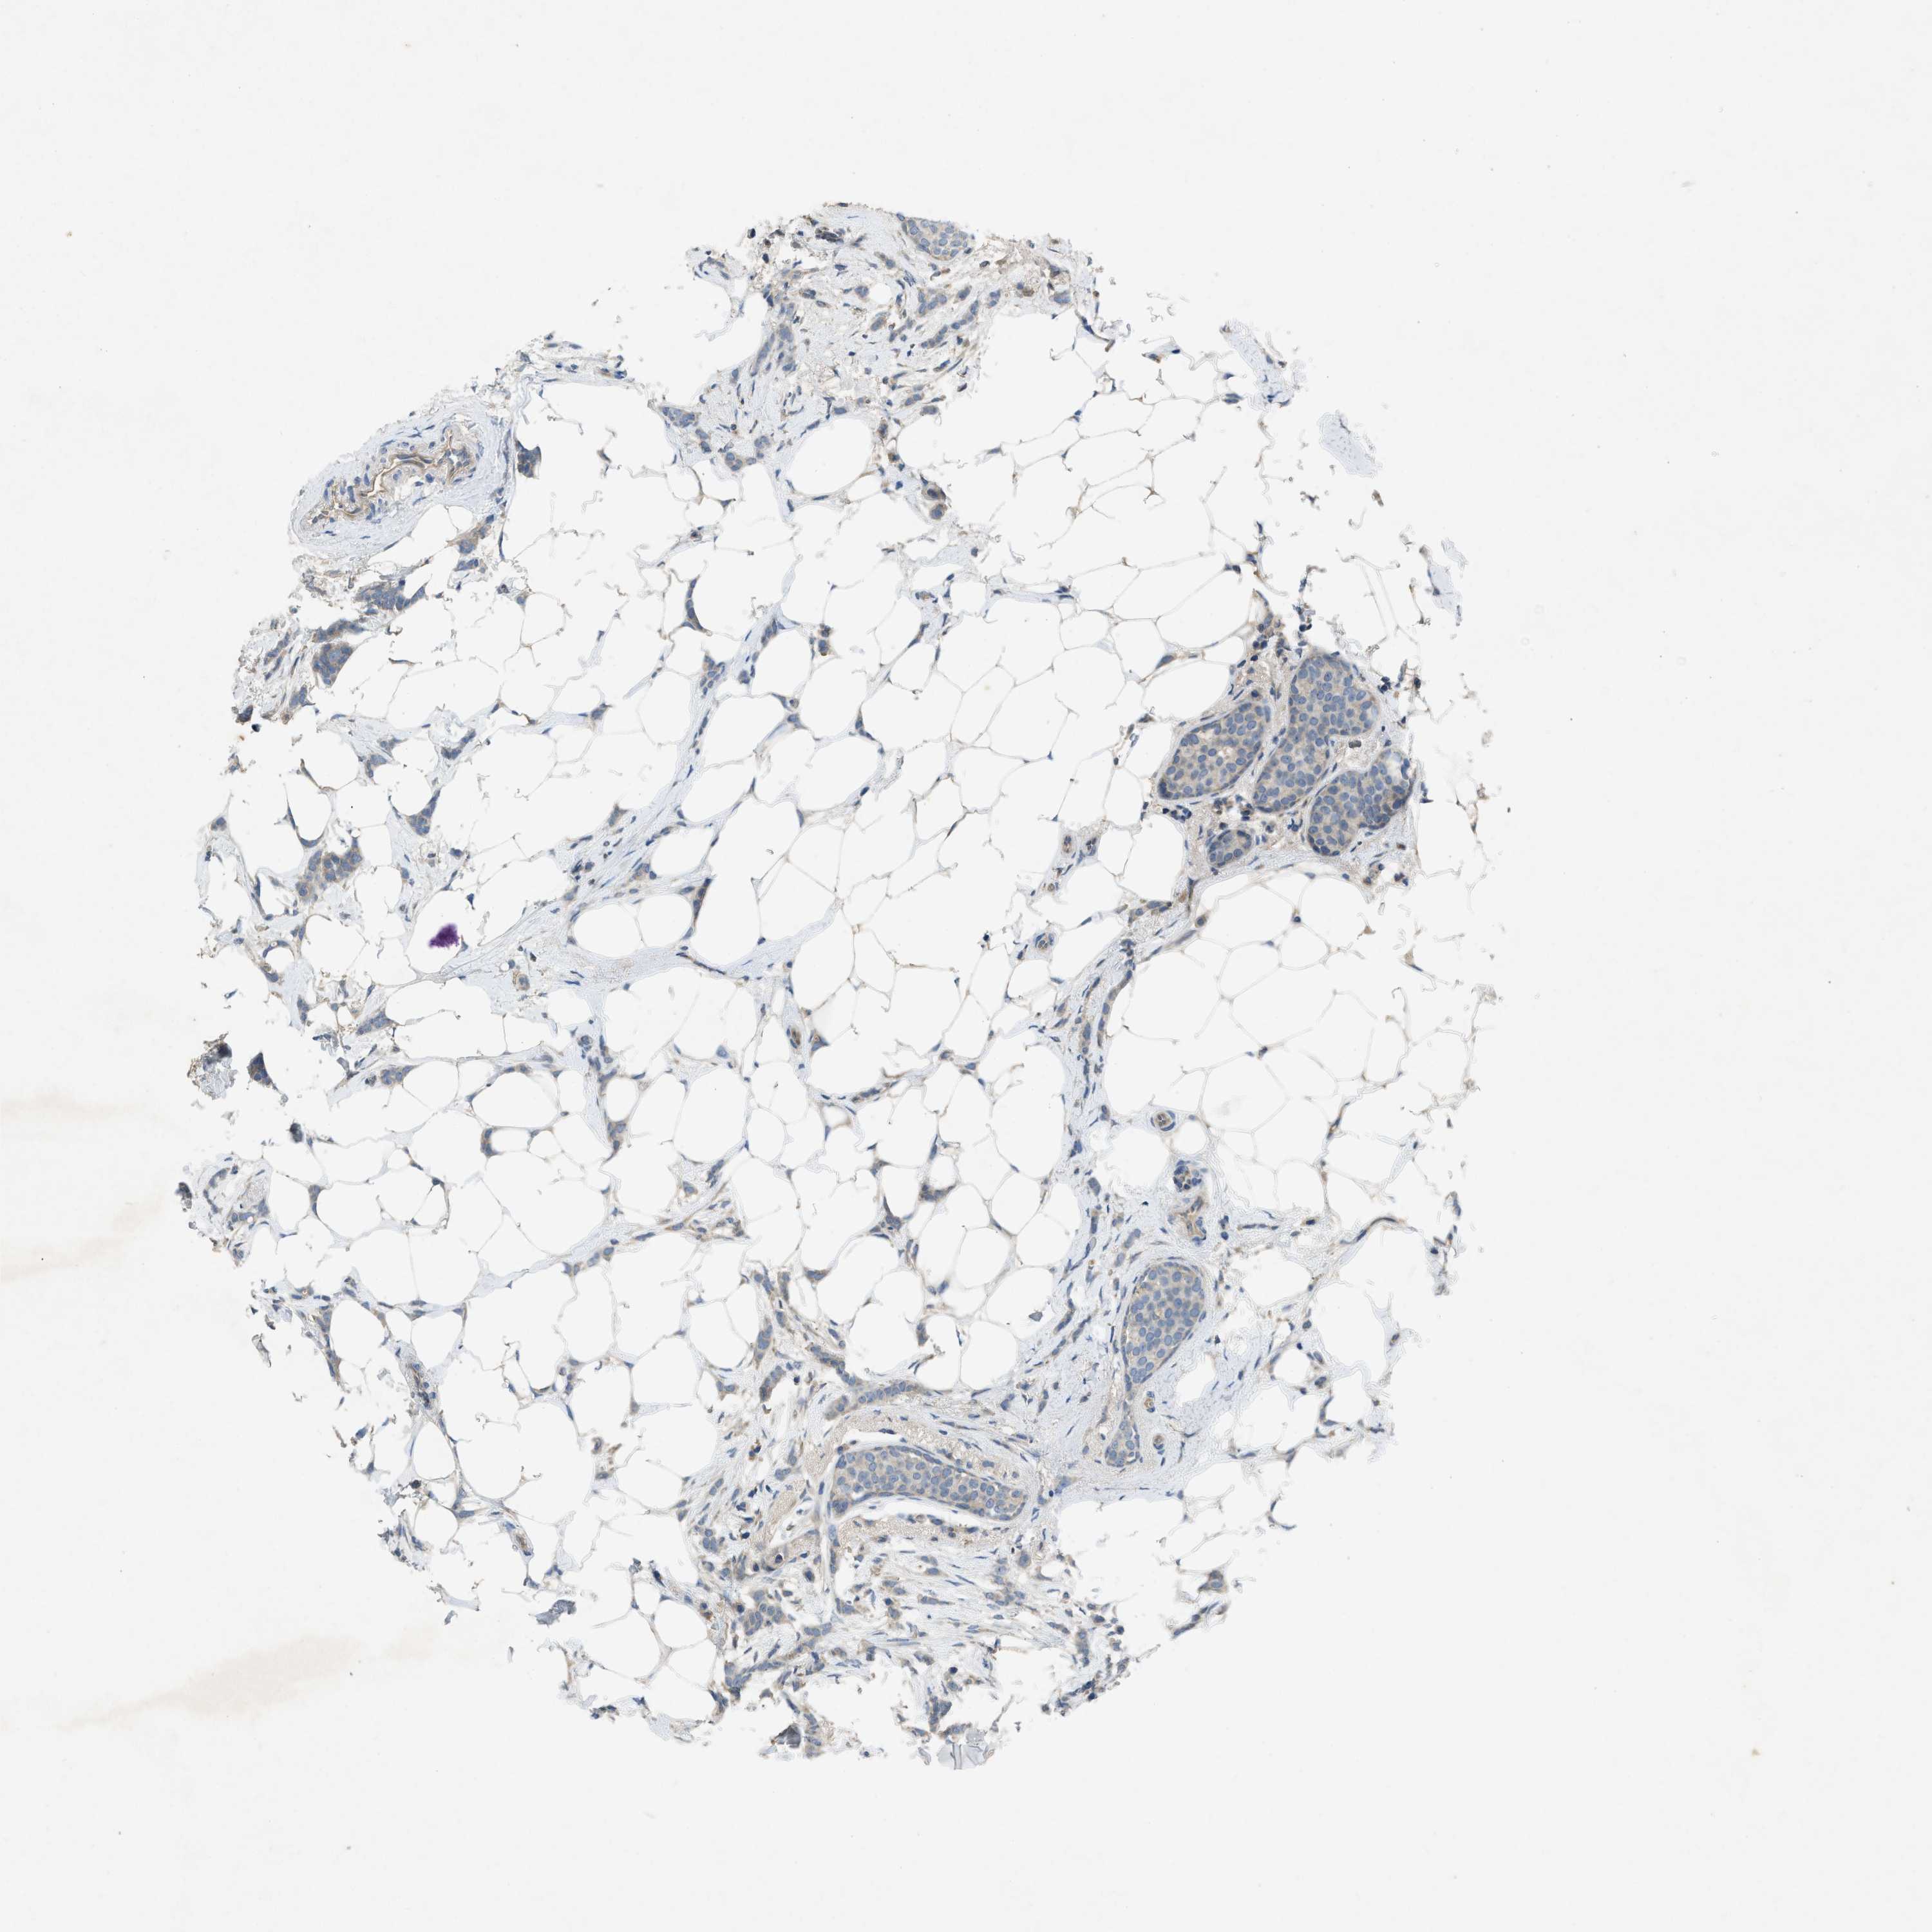

CANCER BREAST CANCER Show tissue menu

BRCA TCGA BRCA VALIDATION PROTEIN EXPRESSION

Breast cancer

Human cancer